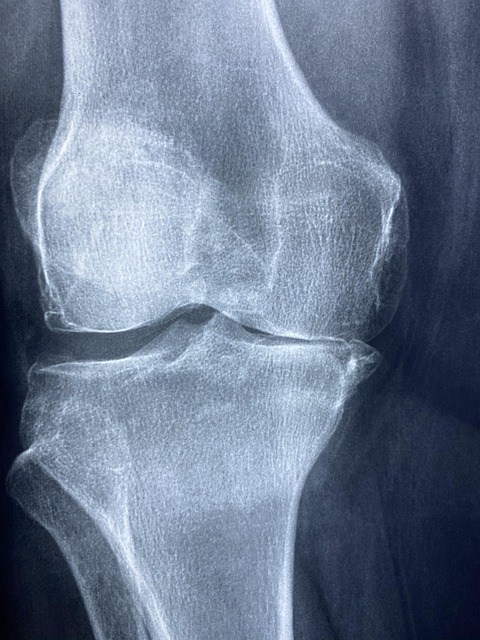

무릎인공관절 수술은 퇴행성 무릎 관절염 환자에게 시행되는 대표적인 수술입니다.

주로 60대 이상에서 발생하는 이 질환은 무릎 연골이 마모되면서 극심한 통증과 운동 제한을 유발하게 되죠.